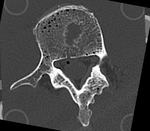

this is the main fixed reference image. All images are ev. aligned into this space this is the main fixed reference image. All images are ev. aligned into this space lleft this is the moving imagethis is the moving image

baseline model follow-up model: contains defect and is acquired in different orientation

• fixed: segmented CT "intact_seg", 0.4 x 0.4 x 0.4 mm voxel size, axial; 284 x 262 x 148 unsigned short image

• moving: segmented CT "defect_seg", 0.5 x 0.5 x 0.50 mm voxel size, axial; 221 x 206 x 113 unsigned short image